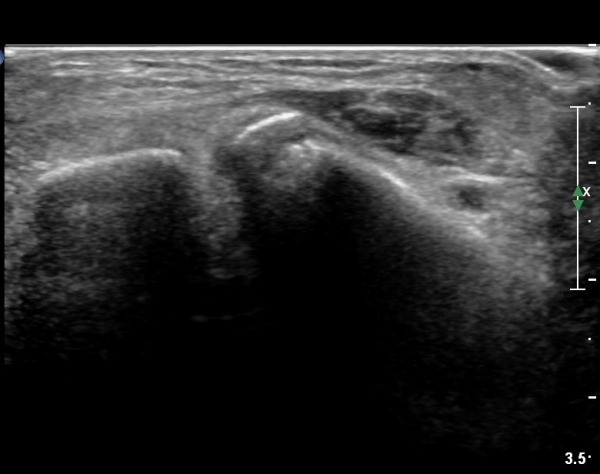

ÃÊÀ½ÆÄ °Ë»ç

CT : avulsion fracture of distal tibia at distal tibiofibulat ligament insertion.